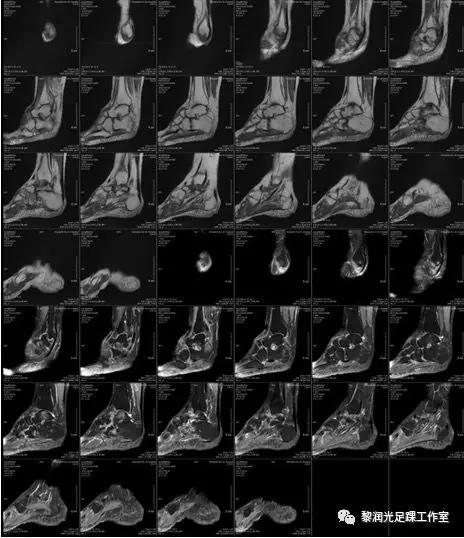

6、足踝影像学评估(X、CT、MRI)